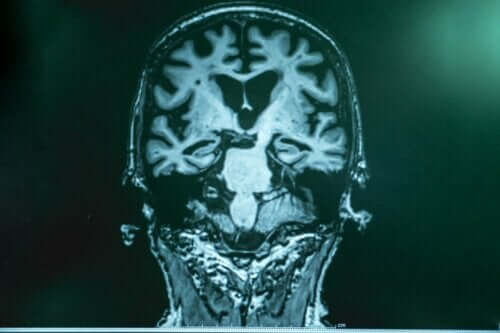

Stimulation af hjernebølger til personer med Alzheimers

Ved du, hvad gammabølger er? Er du klar over fordelene ved stimulation af hjernebølger som behandling af Alzheimers? Fremskridt inden for, og forholdet imellem, videnskab og teknologi har gjort det muligt at udvikle nye behandlingsformer, som er helt fantastiske for disse patienter.

Som vi nævnte i begyndelsen, er Alzheimers oprindelse stadig ukendt. Forskerne er klar over visse patofysiologiske ændringer, som er karakteristiske for denne sygdom.

For eksempel aflejringer af amolyid beta-protein, som ender med at danne et lag omkring neuronerne og gøre dem ubrugelige. Også dannelsen af intracellulære neurofibrillære sammenfiltringer og tilstedeværelsen af fosforyleret tau-protein.